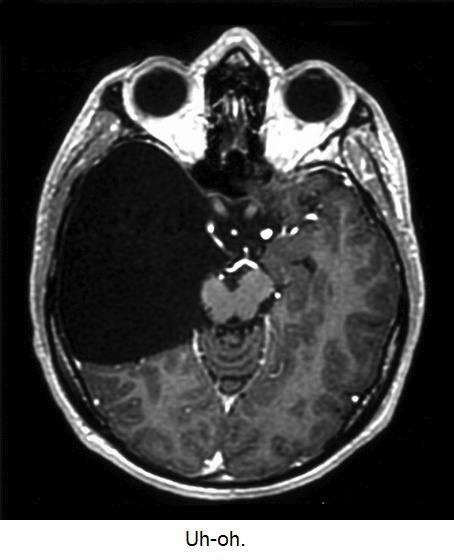

Most places adopt a middle-of-the-road approach. Scans aren't routinely checked by an expert, but if a researcher spots something weird, they can refer the scan to a qualified clinician to follow up. Almost always, there's no underlying disease. Even large, OMG-he-has-a-golf-ball-in-his-brain findings can be benign. But not always.

Out about 5,000 research scans over 5 years, there were 27 referrals. Most were deemed benign... except one which turned out to be potentially very serious - suspected hydrocephalus, increased fluid pressure in the brain, which prompted an urgent referral to hospital for further tests.